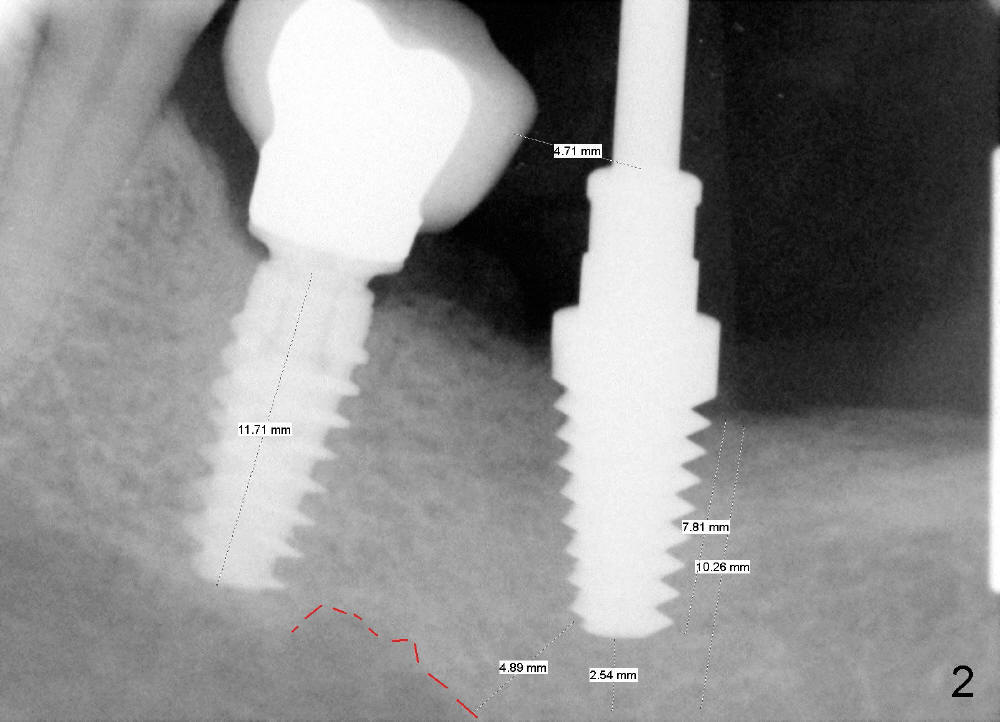

The patient returns for follow up 5 months postop (Fig.8) and abutment insertion 7 months postop (Fig.9,10).